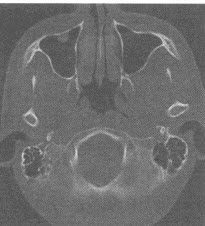

男,58岁,上腹部剑突下胀痛3个月余,近期症状加重,伴消瘦、乏力及柏油样便,无黄疸。体检发现左锁骨上两个肿大淋巴结,无压痛,可移动。肝脾肋下未触及。上腹部CT图像如下

(单选题)根据以上资料,最可能的诊断是()

C:胃窦癌